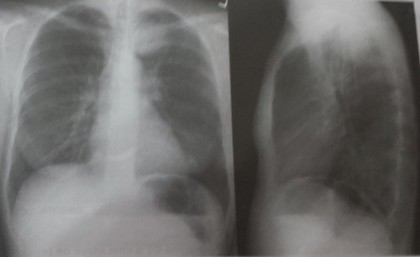

Imaginea radiologică patologică a plămânilor

Radiologic, modificările morfo-funcționale de la nivelul spațiului aerian bronho-alveolar, al interstițiului pulmonar, al patului vascular și al pleurei generează aspecte specifice, care pot fi clasificate în următoarele categorii de bază: hipertransparențe, opacități și imagini mixte. În funcţie de substratul anatomo-patologic, diferitele afecţiuni pulmonare pot produce absorbţia unei cantităţi mai mari de raze X sau invers, absorbţia unei cantităţi mai mici decât la plămânul normal. În primul caz apar voalul şi opacităţile, iar în al doilea caz, hipertransparenţa care poate fi întinsă sau circumscrisă, când apare sub forma de imagini transparente, rotunde, ovalare, liniare sau neregulate.